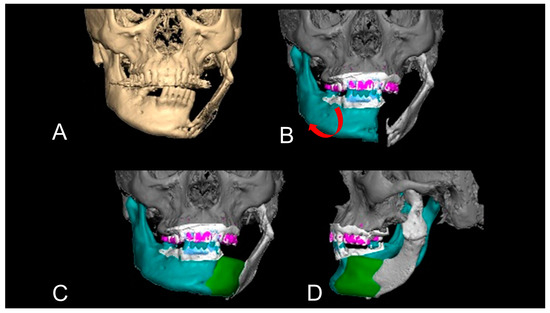

2.7. The Detailed Virtual Reconstruction Technique

2.7.1. Level 1

2.7.2. Level 2

2.7.3. Level 3